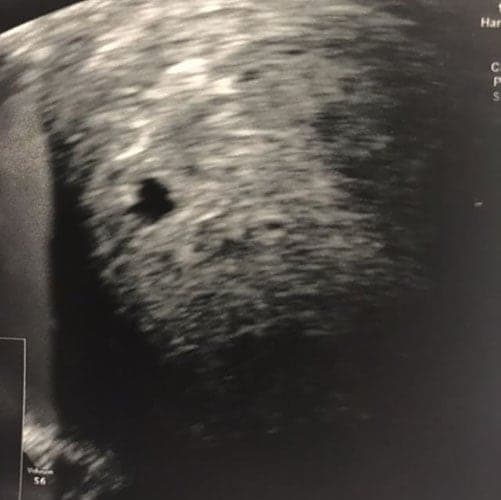

Ultraschallbilder aus dem 3. Trimester (29. bis 40. SSW)

Im dritten Trimester der Schwangerschaft ist das Baby so groß, dass es nicht mehr komplett auf ein Ultraschallbild passt. Nun kann man wunderbare 3D-Ultraschalle des Gesichts machen. In diesem Semester nehmen die Babys nochmal rasant zu und wer Glück hat, kann auf seinem Ultraschall schon erste Gesichtszüge erkennen.